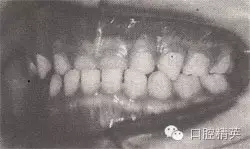

患者,男,4歲,乳牙。磨牙近中關(guān)系。前牙反頜,下頜前突,位置前移。

診斷:乳前牙反頜,安氏Ⅲ類,毛氏Ⅱ¹。

矯治設(shè)計:上頜頜墊式活動矯治器。下頜后退位解剖式頜墊,舌簧推乳上切牙向唇側(cè),調(diào)磨頜墊。

治療時間:1.5個月,乳前牙反頜解除,乳切牙達到正常覆頜、覆蓋。下頜回到正常位置。

圖8-37 安氏Ⅲ類錯頜,乳前牙反頜矯治前后面頜像

矯治后咬合圖